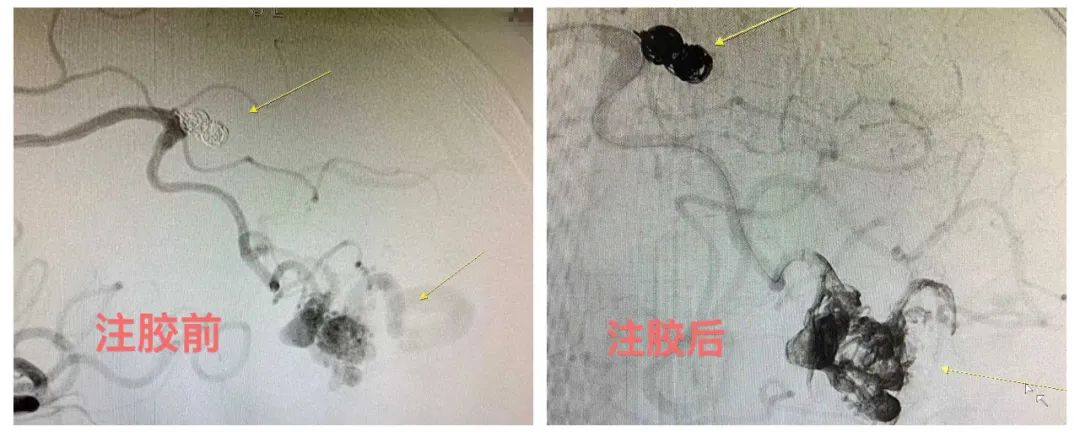

▲注胶前后对比

手术由我科客座教授陈光忠亲自主刀,术中先使用弹簧圈单栓动脉瘤,然后将漂浮导管送至动静脉畸形瘘口,采用液态材料栓塞。Marathon微导管精准到位后使用兼容的弹簧圈小心填塞A4动脉瘤,达到致密栓塞。然后微导管继续朝远端超选,精准到位动静脉畸形巢,使用液体栓塞材料弥散栓塞,畸形巢内动脉瘤被胶水填充后不再显影。因已达到止血治疗目的,按计划决定不再予更改通路栓塞其他供血动脉。术后患者无不适,恢复迅速,目前已顺利出院。